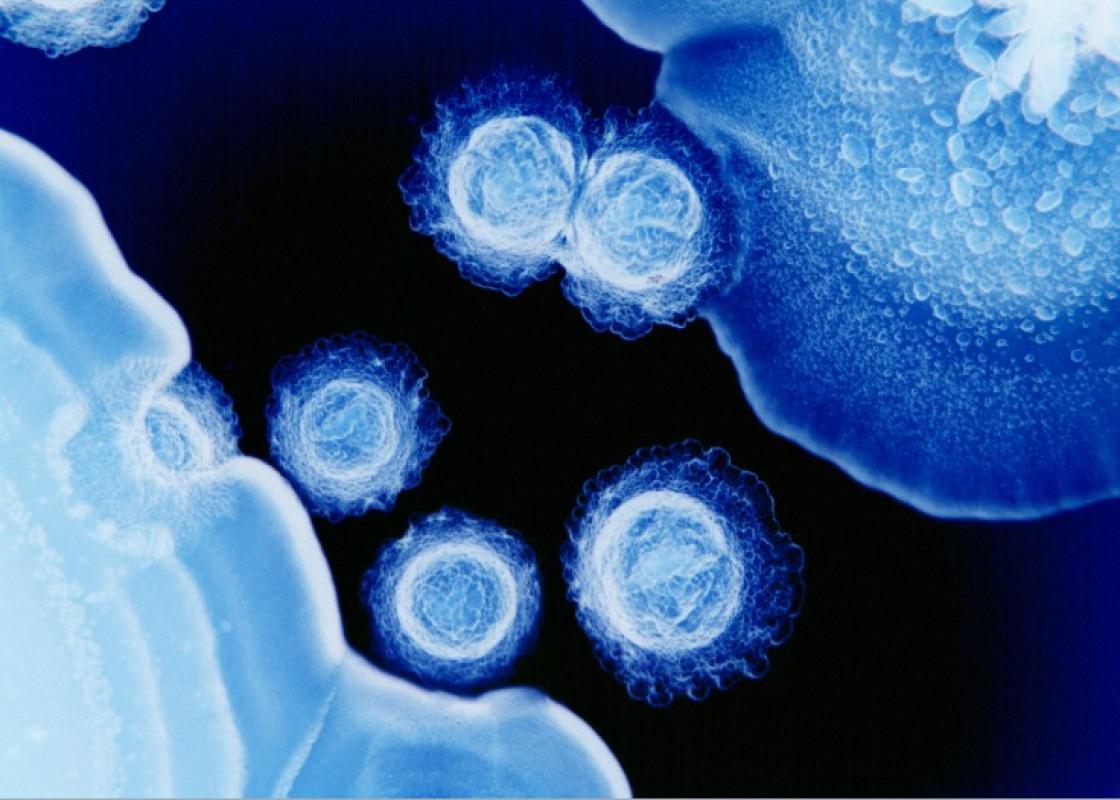

– Vår tiltro til vitenskapelige bilder og deres autoritet må sees i sammenheng med historiske oppfatninger om fotografiet som objektiv representasjon av virkeligheten, som sannhetsvitner om verden rundt oss. Disse forestillingene om fotografiet lever fortsatt videre i dag, og «smitter» over på måten vi forstår vitenskapelige bilder på. Samtidens vitenskapelige bilder er – i enda større grad enn andre bilder vi omgir oss med – brakt fram av en rekke ulike teknikker, som framhever, skjuler og avgrenser. Det brukes for eksempel fluoriserende markører som kan spores med lys, ulike former for mikroskopi som viser henholdsvis tverrsnitt og overflater av vevsprøver, samt omgjøring av todimensjonale bilder til tredimensjonale rekonstruksjoner. Det vi ser er en teknisk avansert og konstruert framstilling av virkeligheten, ikke en avduking av den, framholder Johansen.

Forskere kjenner godt til alle grepene som skal til for å få fram et illustrerende bilde av for eksempel en kreftcelle, og alle utvelgelsene og tilpasningene som er gjort før prøven legges under mikroskopet. I offentligheten ellers, derimot, ser Johansen at det stadig spilles på at bildene «lar oss se naturens under».

Med sin bakgrunn fra kunst- og medieforskning er Johansen interessert i de vitenskapelige bildenes estetikk. Det er også vitenskapfolk selv. Mange av bildene hun tar for seg er hentet fra konkurransen Wellcome Image Awards.

– Her konkurrerer forskere og medisinske fotografer om hvem som har produsert, ikke bare om det mest vitenskaplige bildet, men også det mest slående bildet. Vakre farger, fine former og lekker komposisjon verdsettes, med den begrunnelse at dette er viktig i kommunikasjonen til offentligheten. Samtidig holder det ikke at bildet er fascinerende, det må også argumenteres for at det er nyttig, forteller Johansen. –Her spiller nok også bildets symbolverdi inn, slik som når et bilde av egg- og sædceller fra kunstig befruktning blir til et symbol på livets mysterium.